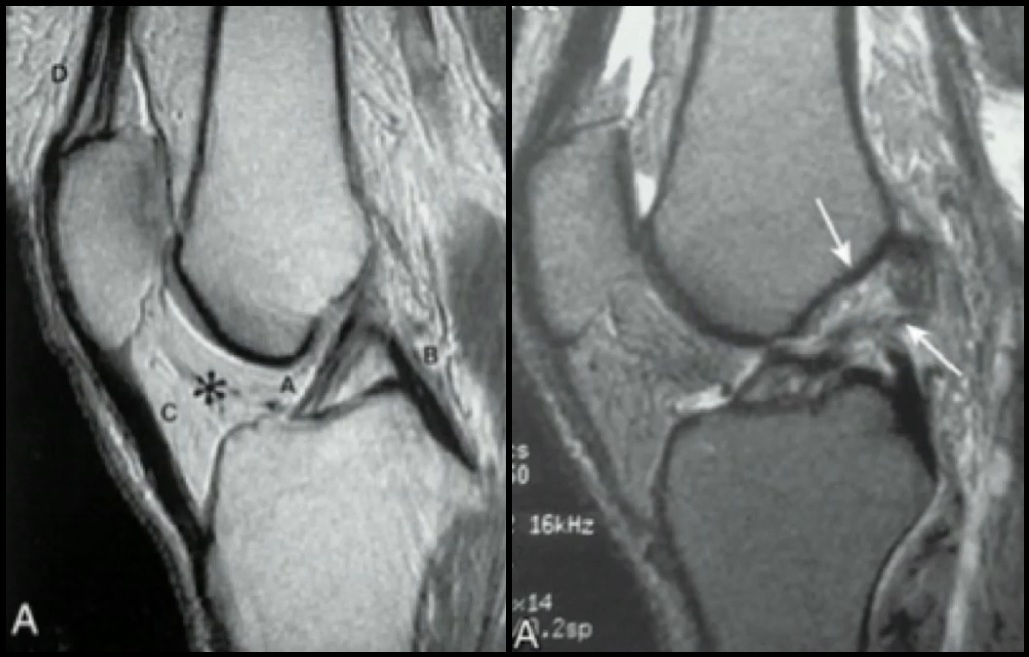

Q

Lesões do LCA

Exame de Imagem: RNM?

A

Lesão do LCA → Melhor visto no corte Sagital

Lesão Osteocondral → Edema Ósseo

Lesões Meniscais